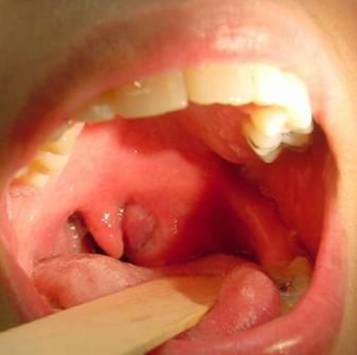

• Фарингоскопия. Наиболее информативный метод диагностики. Позволяет визуально определить наличие флюктуирующего шаровидного выпячивания околоминдаликовой клетчатки, покрытого гиперемированной слизистой оболочкой. Часто на его поверхности имеется небольшой участок желтоватого цвета - зона будущего прорыва гнойных масс. Образование может вызывать асимметрию зева - смещение язычка в здоровую сторону, оттеснение небной миндалины. Локализация гнойника зависит от клинической формы патологии.